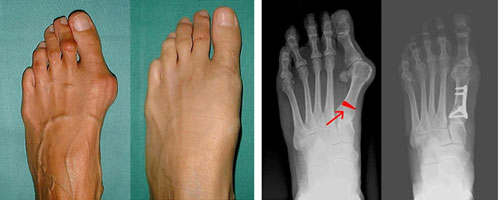

Перед началом лечения врач обязательно диагностирует степень поражения стопы. Так, например, при лёгкой степени угол отклонения большого пальца не превышает 11 – 12 градусов. При этом каких-либо изменений в мышцах не наблюдается.

Средняя степень деформации будет иметь больший угол отклонения — от 20 до 40 градусов. При этом на рентгенограмме будет наблюдаться подвывих сустава I пальца ноги.

При тяжёлой степени деформация будет ещё более значительной и угол отклонения будет более 40 градусов. Присутствует внутренний выворот первого пальца. Это самая тяжёлая степень поражения.

При плоско вальгусной деформации стопы сильно увеличивается угол между первым и вторым пальцем. При этом кости первого пальца начинают смещаться внутрь, а сам он смещается кнаружи. Из-за этого на боковой поверхности ноги начинает образовываться бугорок, который в народе носит название «косточка на ноге». Постепенно палец всё больше и больше отклоняется от своего нормального положения и начинает «смотреть» не внутрь, а наружу.

В запущенных случаях применяется только хирургическое лечение, причём может быть выбран один из нескольких методов, например, простое удаление нароста, дистальная и проксимальная остеотомия, операция по фиксации сустава, имплантация самого поражённого сустава, либо один из более 90 других индивидуальных методик хирургического лечения.